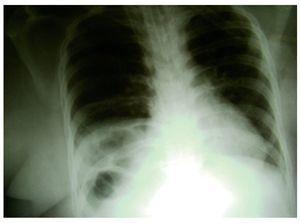

Una pacient de 22 anys, amb diagnòstic de SD, va ingressar al servei d'urgències amb febre i dispnea. La pacient estava sotmesa a un seguiment regular i no presentava comorbiditats, tret de la SD. Tenia una tos seca persistent des de feia una setmana. A l'exploració física inicial presentava 39,2 °C de febre, cianosi i so respiratori reduït a la part baixa del pulmó dret. A l'avaluació analítica es va detectar leucocitosi i acidosi respiratòria greu. Els paràmetres bioquímics eren normals. La pacient, hemodinàmicament estable, va rebre tractament amb oxigen nasal i va ser controlada de prop. A l'exploració posterior amb radiografia del tòrax, es van observar nanses intestinals al costat dret del tòrax amb radioopacitat infiltrant conforme a pneumònia (fig. 1). El pulmó esquerre no presentava cap afecció.

Figura 1 En la radiografia toràcica s'observen nanses intestinals al costat dret del tòrax.